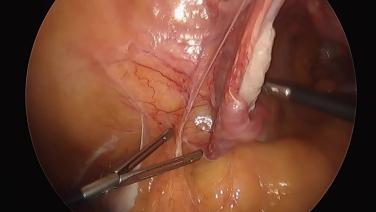

Total Laparoscopic Hysterectomy - Divide Broad Ligament

Total Laparoscopic Hysterectomy - Transect Utero-Ovarian Ligaments

Total Laparoscopic Hysterectomy - Ligate & Divide Mesosalpinx

Total Laparoscopic Hysterectomy - Ligate & Divide Round Ligaments

Total Laparoscopic Hysterectomy - Anatomic Survey